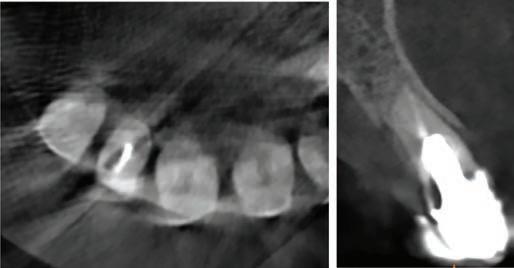

In order to proceed with the digital planning workflow, a series of clinical records were made, which included pre-operative radiographs, clinical photographs and digital intra-oral scans (3Shape; TRIOS, Copenhagen, Denmark). A photorealistic 3D tessellation, or triangulation, of the facial features was generated in real colours using the Face Hunter scanner (Zirkonzahn Srl; Gais, Italy), while patient-specific occlusal information was captured and recorded using the PlaneSystem (Zirkonzahn Srl; Gais, Italy) (Figure 3). When combined, these records allow for efficient communication from the clinic to the dental

laboratory, regarding the precise spatial arrangement of the pre-operative dentition as it relates to key aesthetic and biomechanical determinants of a harmonised tooth arrangement,9 including:

1. The facial mid-line: this in turn determines the ideal dental mid-line location.10

2. The inter-pupillary line and natural head position: this determines the ideal occlusal plane of the maxillary anterior teeth as viewed from the patient’s front.11,12

3. The smile display: this is a determinant of the incisal edge positions and therefore the ideal tooth lengths and gingival margin locations when viewed from the patient’s front and side profiles.13

4. The ala-tragal line: this is a key determinant of the maxillary occlusal plane as viewed from the patient’s side profile.14

5. Maxillo-mandibular relationships: from which incisor inclinations and interarch static and dynamic occlusal factors may be determined.15

FIGURE 3: Identification of the ala-tragal line with black marker in preparation for recording of occlusal-specific information using the PlaneSystem. Threedimensional facial tessellation scanning, achieved with Face Hunter, permits merging of an intra-oral scan using Zirkonzahn.Modifier software. Key biomechanical and aesthetic landmarks are now conveniently available for reference at the dental laboratory.